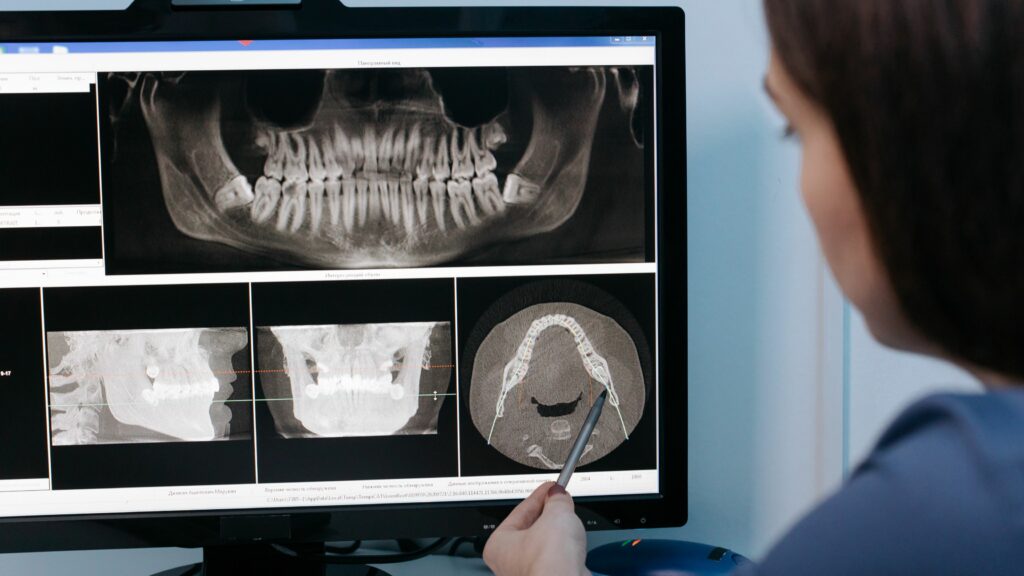

Poco osso: la panoramica iniziale

Dalla panoramica dentale si è notato che gli apici dei premolari confinavano con il seno mascellare e, con molta probabilità, una volta estratti questi denti, ci sarebbe stato poco osso a disposizione per inserire gli impianti. Anche nella zona molare la quantità di osso era deficitaria, solo nella zona retro molare, grazie anche alla valutazione della TAC Cone Beam, si è individuata una porzione di osso residuo da potere sfruttare per l’inserimento degli impianti.

Proprio per la difficoltà ad individuare porzioni di osso residuo dove inserire gli impianti, si è deciso di avvalerci dell’aiuto della tecnologia computer guidata e di un software dedicato. Siamo cosi riusciti a trovare una zona di osso nella zona retro-molare, che ci ha consentito di pianificare in quell’area il posizionamento di un impianto.